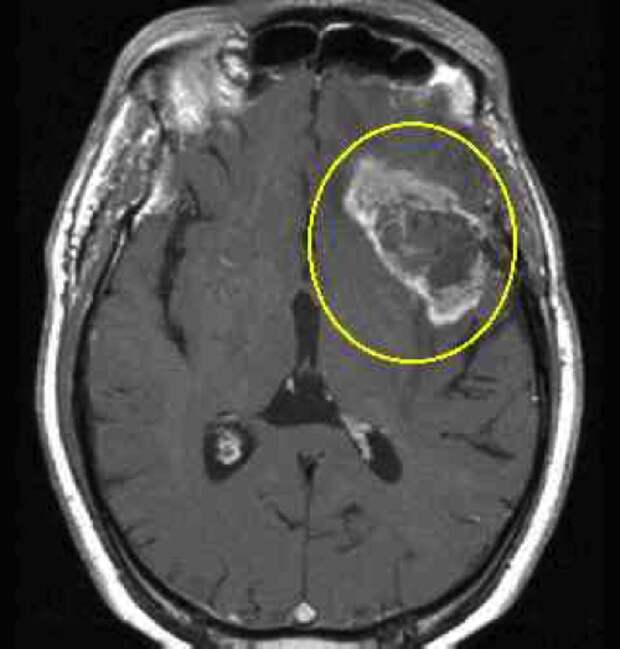

Мрт Раков Фото